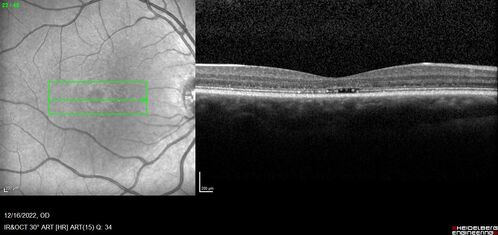

Stargardt Disease - Very Mild - 24 year old

This patient has 3 different ABCA4 mutations. His mother and sister have stargardts and his father has RP. His sisters images are also on Retinagallery.com

Stargardt Sibling - ABCA4 3 mutations